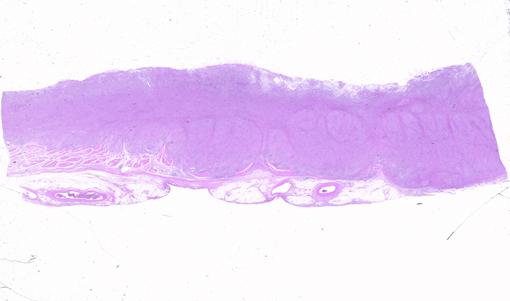

潰瘍限局型の胃癌に類似した形態を示した進行胃悪性リンパ腫の割面ルーペ像  病変の中央部での割面における組織ルーペ像です。胃壁は粘膜固有層(m)、粘膜下層(sm)、固有筋層(mp)、漿膜下層(ss)の全層にわたって、腫瘍細胞で置き換えられています。腫瘍細胞はびまん性に、浸潤増殖しています。

疾患(病理主体)の分類悪性リンパ系腫瘍/悪性リンパ腫

部位(臓器別)胃(部位)/体部

腫瘍の肉眼分類2型(潰瘍限局型)/

病変の最大径(ミリ)40以上

腫瘍の深達度ss(a1)